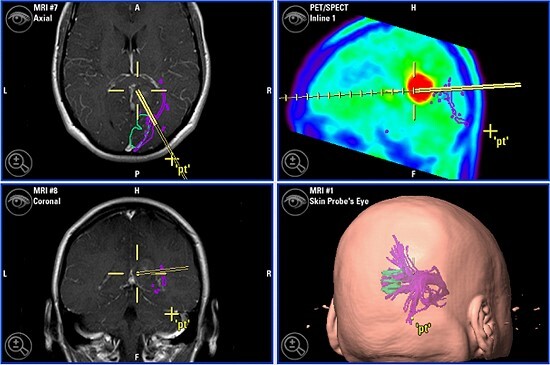

WKK-Neurochirurgie rüstet bei Geräten zur Operationsplanung auf - Qualitätssteigerung durch „Mercedes unter den Systemen"